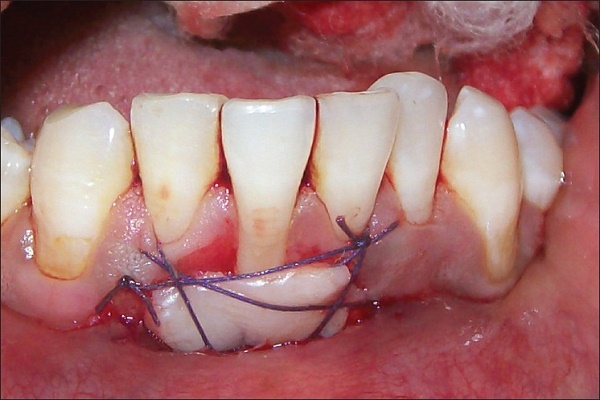

A free gingival graft procedure is used to thicken the gum tissue, as thicker gum tissue is more resilient to trauma and inflammation. During the procedure, a small piece of tissue is taken from the roof of your mouth and relocated to the area of recession. Both areas generally heal quite quickly.

CONNECTIVE TISSUE GRAFT

A connective tissue graft is used to thicken the gum tissue and cover exposed roots. A piece of tissue is taken, relatively painlessly, from an inner layer of the palate or another donor source and is transferred to the area. After this procedure, patients need to avoid chewing in this area of of the mouth for a couple of weeks. A mouthwash will be recommended to keep the area clean.